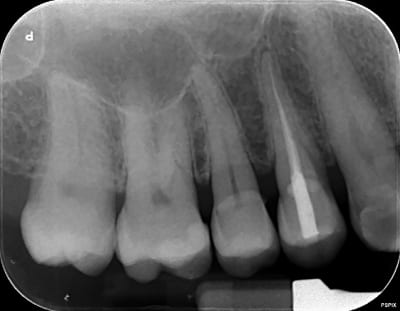

La qualité de la rx est pas terrible car j'ai impr ecran via teamviewer, je ne suis pas au cab.

au vu de cette image ( mauvaise comme tu dis ) moi je couronne pas

En tout cas, au vu de la cavité d'accès j'aurai aussi un doute.